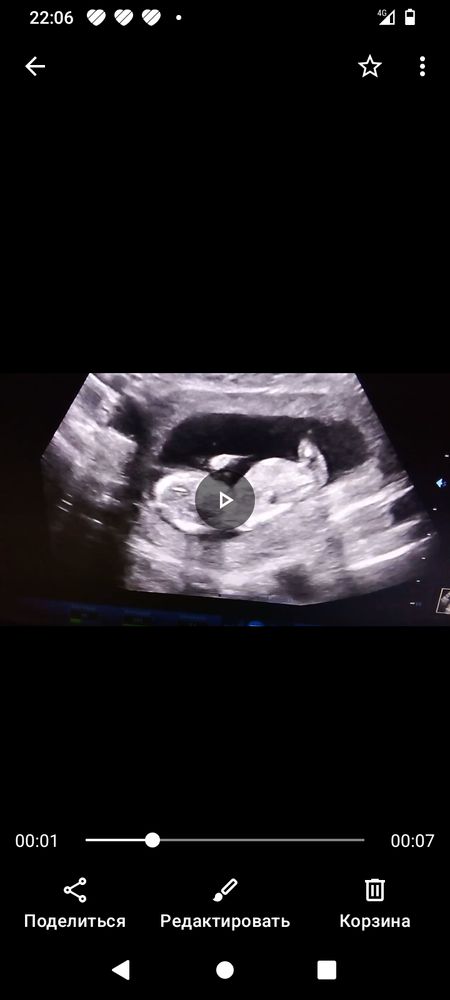

Определение пола в 13 недель

Изображение Вот еще фото, это я все записывала с видео Стелла,

Я конечно не профи, но если я правильно поняла фото узи, то на фото скорее девочка чем мальчик, надеюсь я ошибаюсь и будет так как вам хочется.

Ошибка 80%. Рано еще

На 1 скрине сказали скорее всего мальчик, 2 следующих подтвердили. но мб и не точно, чтоб наверняка анализ сдайте